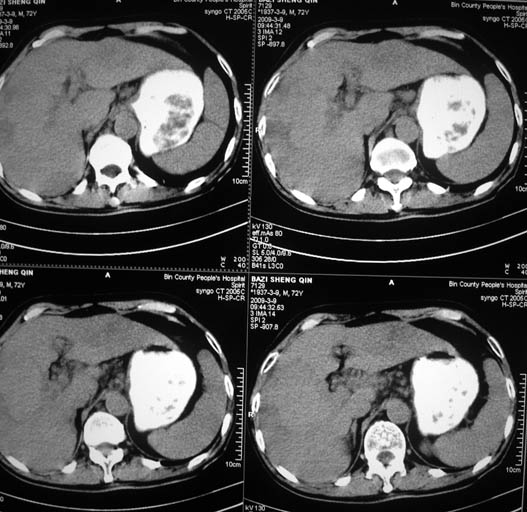

以下是引用ct诊断高手在2009-3-9 21:44:00的发言:[br]增强观看肝内强化及小网膜淋巴结。排除血管瘤肝脓肿

以下是引用影象小泰斗在2009-3-9 22:06:00的发言:[br]肝脏多发占位,不好说是原发肝癌或肝转移瘤!建议强化!

以下是引用黑白光影在2009-3-9 22:19:00的发言:[br]肝脏多发性占位性病变,腹膜后多发淋巴结肿大,建议行ct增强扫描检查。

以下是引用随光逐影在2009-3-9 22:15:00的发言:[br]1)肝脏多发性占位性病变(肝癌?肝转移瘤?);建议行ct增强扫描检查。2)腹膜后多发淋巴结肿大。